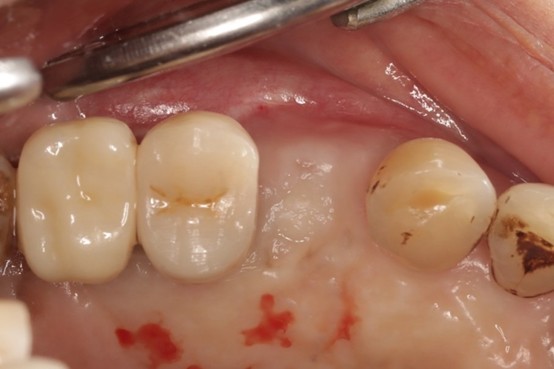

臨床個案治療紀錄

治療前影像